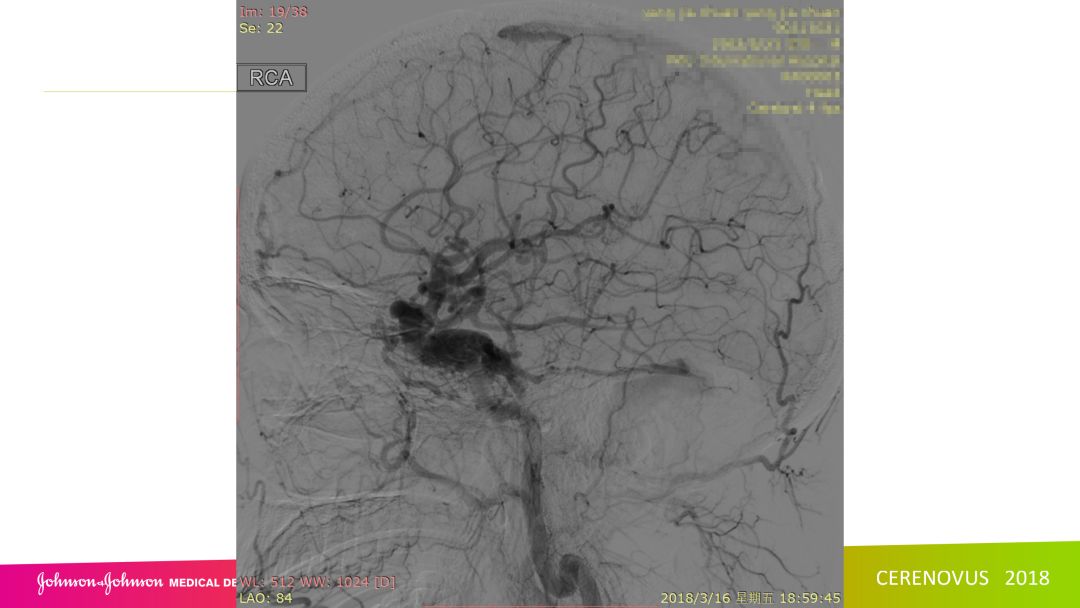

复合手术治疗海绵窦区硬脑膜动静脉瘘一例